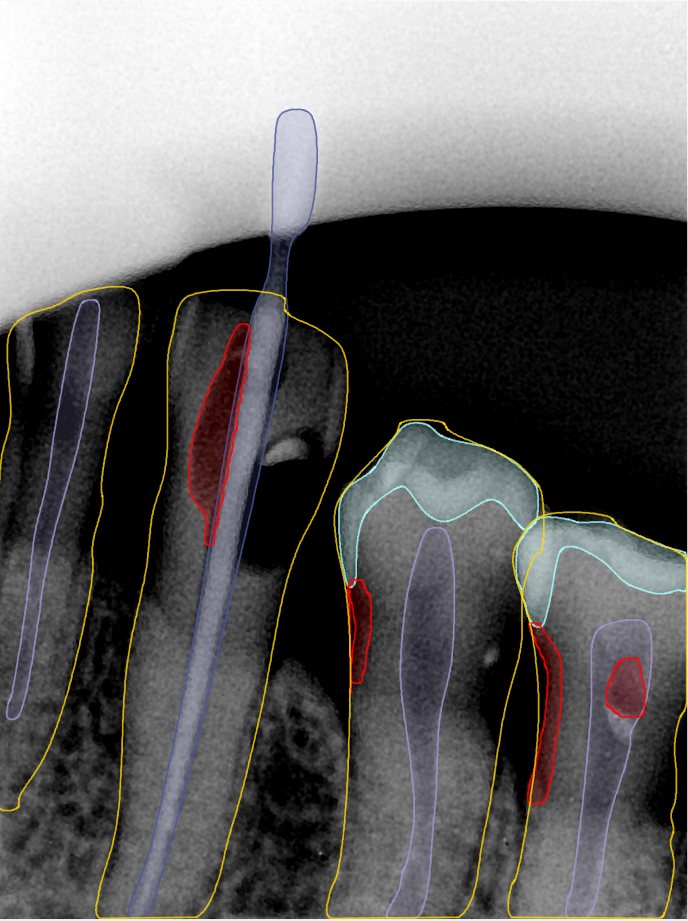

CR/DR 牙齿分割阶段记录

当前进展

- 完成了 CR/DR 牙齿相关分割训练

- 当前结果已经达到阶段预期,但仍有细节问题需要继续处理

相关测试

遇到的问题

- 训练过程中出现过 mask 下移问题

- 部分结果会出现 box 填充异常

- mask 边缘仍然有比较明显的锯齿感

第二版算法问题测试

| 第一版 | 第二版 | 是否解决 | |

|---|---|---|---|

![]() | ![]() ![]() 边角识别有问题 龋齿识别不全 牙髓识别不全 | ![]() | 解决 |

![]() | ![]() 边角识别有问题 识别信息有误 自查(牙冠识别不全) | ![]() | 解决 |

![]() | ![]() ![]() 边角识别有误 大范围填充识别遗漏 | ![]() | 解决 |

![]() | ![]() 识别信息不全 | ![]() | 解决 |

![]() | ![]() ![]() 边角问题 牙胶识别不全 牙冠识别不全 | ![]() | 解决 |

![]() 换图片 | ![]() | ![]() 牙冠部分稍微白了一些就识别成小范围修补,部分判断异常 | 部分解决,修复类略敏感,牙冠部分稍微白了一些就识别成小范围修补,部分判断异常。 |

![]() | ![]() ![]() 牙冠识别不全 牙髓不全 根尖炎龋齿识别有误 | ![]() | 解决 |

![]() | ![]() | ![]() | 解决 |

![]() 换图片 | ![]() | ![]() | 解决 |

![]() | ![]() 牙冠识别有误 | ![]() | 解决 |

![]() 换图片 | ![]() ![]() 边角识别有误 | ![]() 修复类敏感 | 部分解决,图像过白,导致修复类判断异常。 |

![]() 换图片 | ![]() 牙冠识别不全 | ![]() 修复类敏感 | 部分解决,图像过白,导致修复类判断异常 |

结论:修复类出现了不鲁棒的情况,后续需要加入轮廓的扩充数据进行增强。